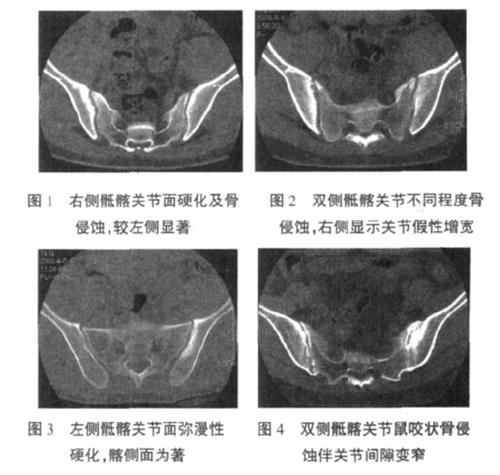

2、骶髂關(guān)節(jié)炎疼痛感強(qiáng)烈:時(shí)常伴有放射性疼痛,在立位屈曲時(shí)產(chǎn)生嚴(yán)重腰痛,或造成一側(cè)骶髂關(guān)節(jié)向前或向后的半脫位,所以骶髂關(guān)節(jié)炎的癥狀臨床有跛行足及足后根痛;骶髂關(guān)節(jié)炎在進(jìn)行關(guān)節(jié)后防穿刺時(shí)有膿液流出,X線(xiàn)早期無(wú)明顯改變,晚期關(guān)節(jié)面硬化顯示蟲(chóng)蝕樣改變,關(guān)節(jié)面增厚,有時(shí)有死骨;患病的關(guān)節(jié)出現(xiàn)紅、腫、熱、痛的癥狀。